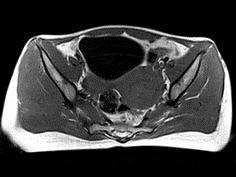

问题 35岁女性患者,曾行剖宫产手术,有痛经史5年,近来加重,行MRI检查,如图所示,请选择正确的答案 ( )

选项 A、卵巢表皮样囊肿 B、卵巢粘液性囊肿 C、子宫颈癌 D、卵巢囊肿 E、子宫内膜异位症

答案 E